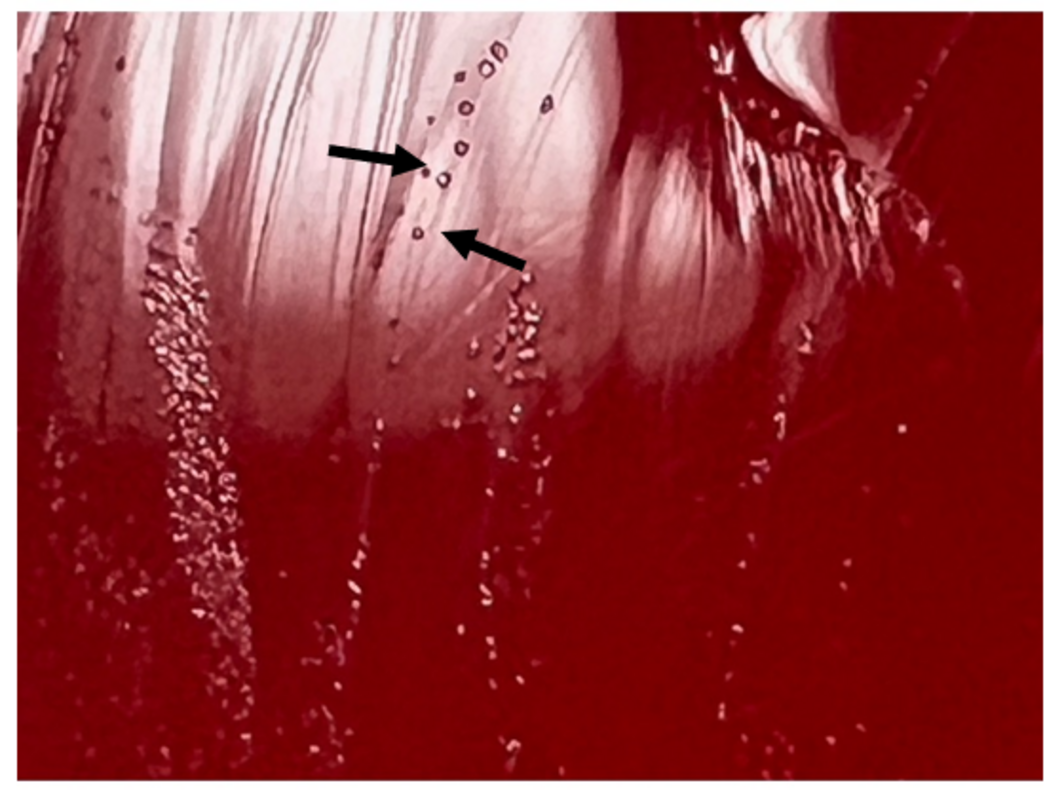

При окрашивании жидкости по Граму не было обнаружено микроорганизмов. Через 48 часов инкубации на кровяном агаре наблюдался рост от небольшого до умеренного количества точечных прозрачных колоний, с характерным миниатюрным видом центральной области плотного роста и периферийной менее плотной (илл. 1). При ближайшем рассмотрении колонии имели вид "яичницы глазуньи" (илл. 2). На среде МакКонки рост отсутствовал. Окончательная идентификация методом MALDI-TOF показала наличие Mycoplasma hominis.

Иллюстрация 1. Рост на кровяном агаре четких мелких колоний M. hominis.

Иллюстрация 2. Характерные колонии организма с периферическим ростом и более плотным центральным ростом внешне напоминающим жареное яйцо.

Отсутствие клеточных стенок создает как диагностические, так и клинические трудности. Микоплазмы не видны на обычных мазках, окрашенных по Граму. Вместо клеточной стенки они имеют трехслойную мембрану, состоящую из стеролов. Когда они начинают расти в культуре, колонии становятся маленькими и имеют на агаре вид «жаренных яиц». Из всех видов микоплазм, M. hominis наименее привередлива и является самой распространенной микоплазмой, выделяемой на обычных культуральных агаровых средах. Диагностика часто осуществляется с помощью молекулярного тестирования. Этот вид часто обнаруживается при коинфекции с Trichomonas vaginalis и считается симбиотическим.